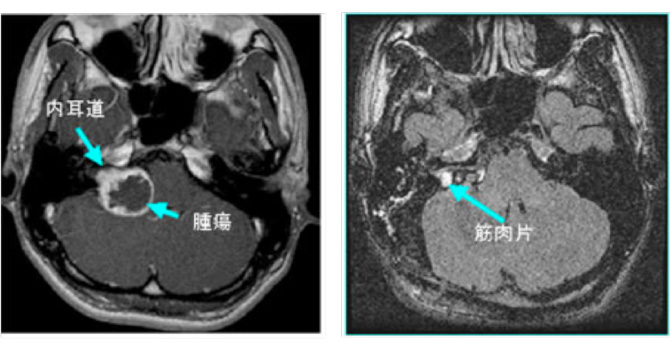

図4:神経繊維腫症2型の症例

42歳女性 両側の聴神経腫瘍をみとめる。NF2の症例。両側とも聴覚は良好であり、大きい方の腫瘍をまず摘出。聴覚は術後やや低下したが温存された。右の小型聴神経腫瘍は拡大傾向なく経過を観察している。

▲ 術前MRI

▲ 術前の聴覚

▲ 術後MRI 左側の腫瘍は被膜を残して摘出されている

▲ 術後左聴覚は25dBまで低下したが、良好な温存。